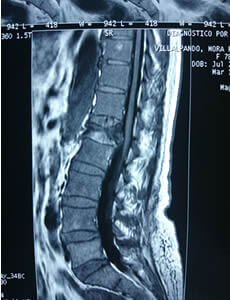

Conóce los síntomas que se presentan para una cirugía de columna.Dolor de Espalda baja

Este es el más común de todos.